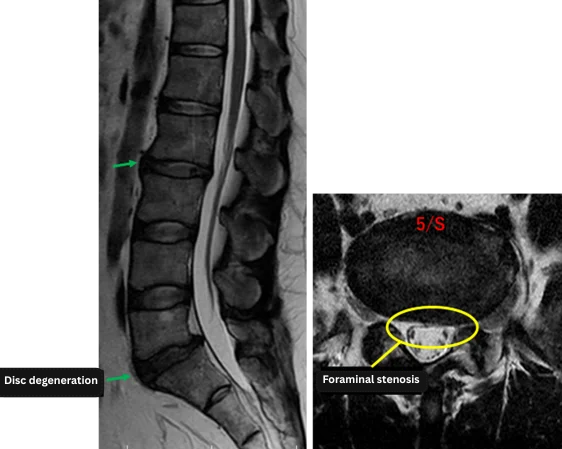

Imaging and findings

L1/2: No abnormalities

L2/3: No significant abnormalities, but early signs are present (treated upon patient’s request).

L3/4: No abnormalities

L4/5: No abnormalities

L5/S: Degeneration, disc bulging, left foraminal stenosis

The above findings were also observed on the imaging.

Degeneration, bulging, and left foraminal stenosis at L2/3 and L5/S are considered likely contributors to the patient’s primary symptoms.